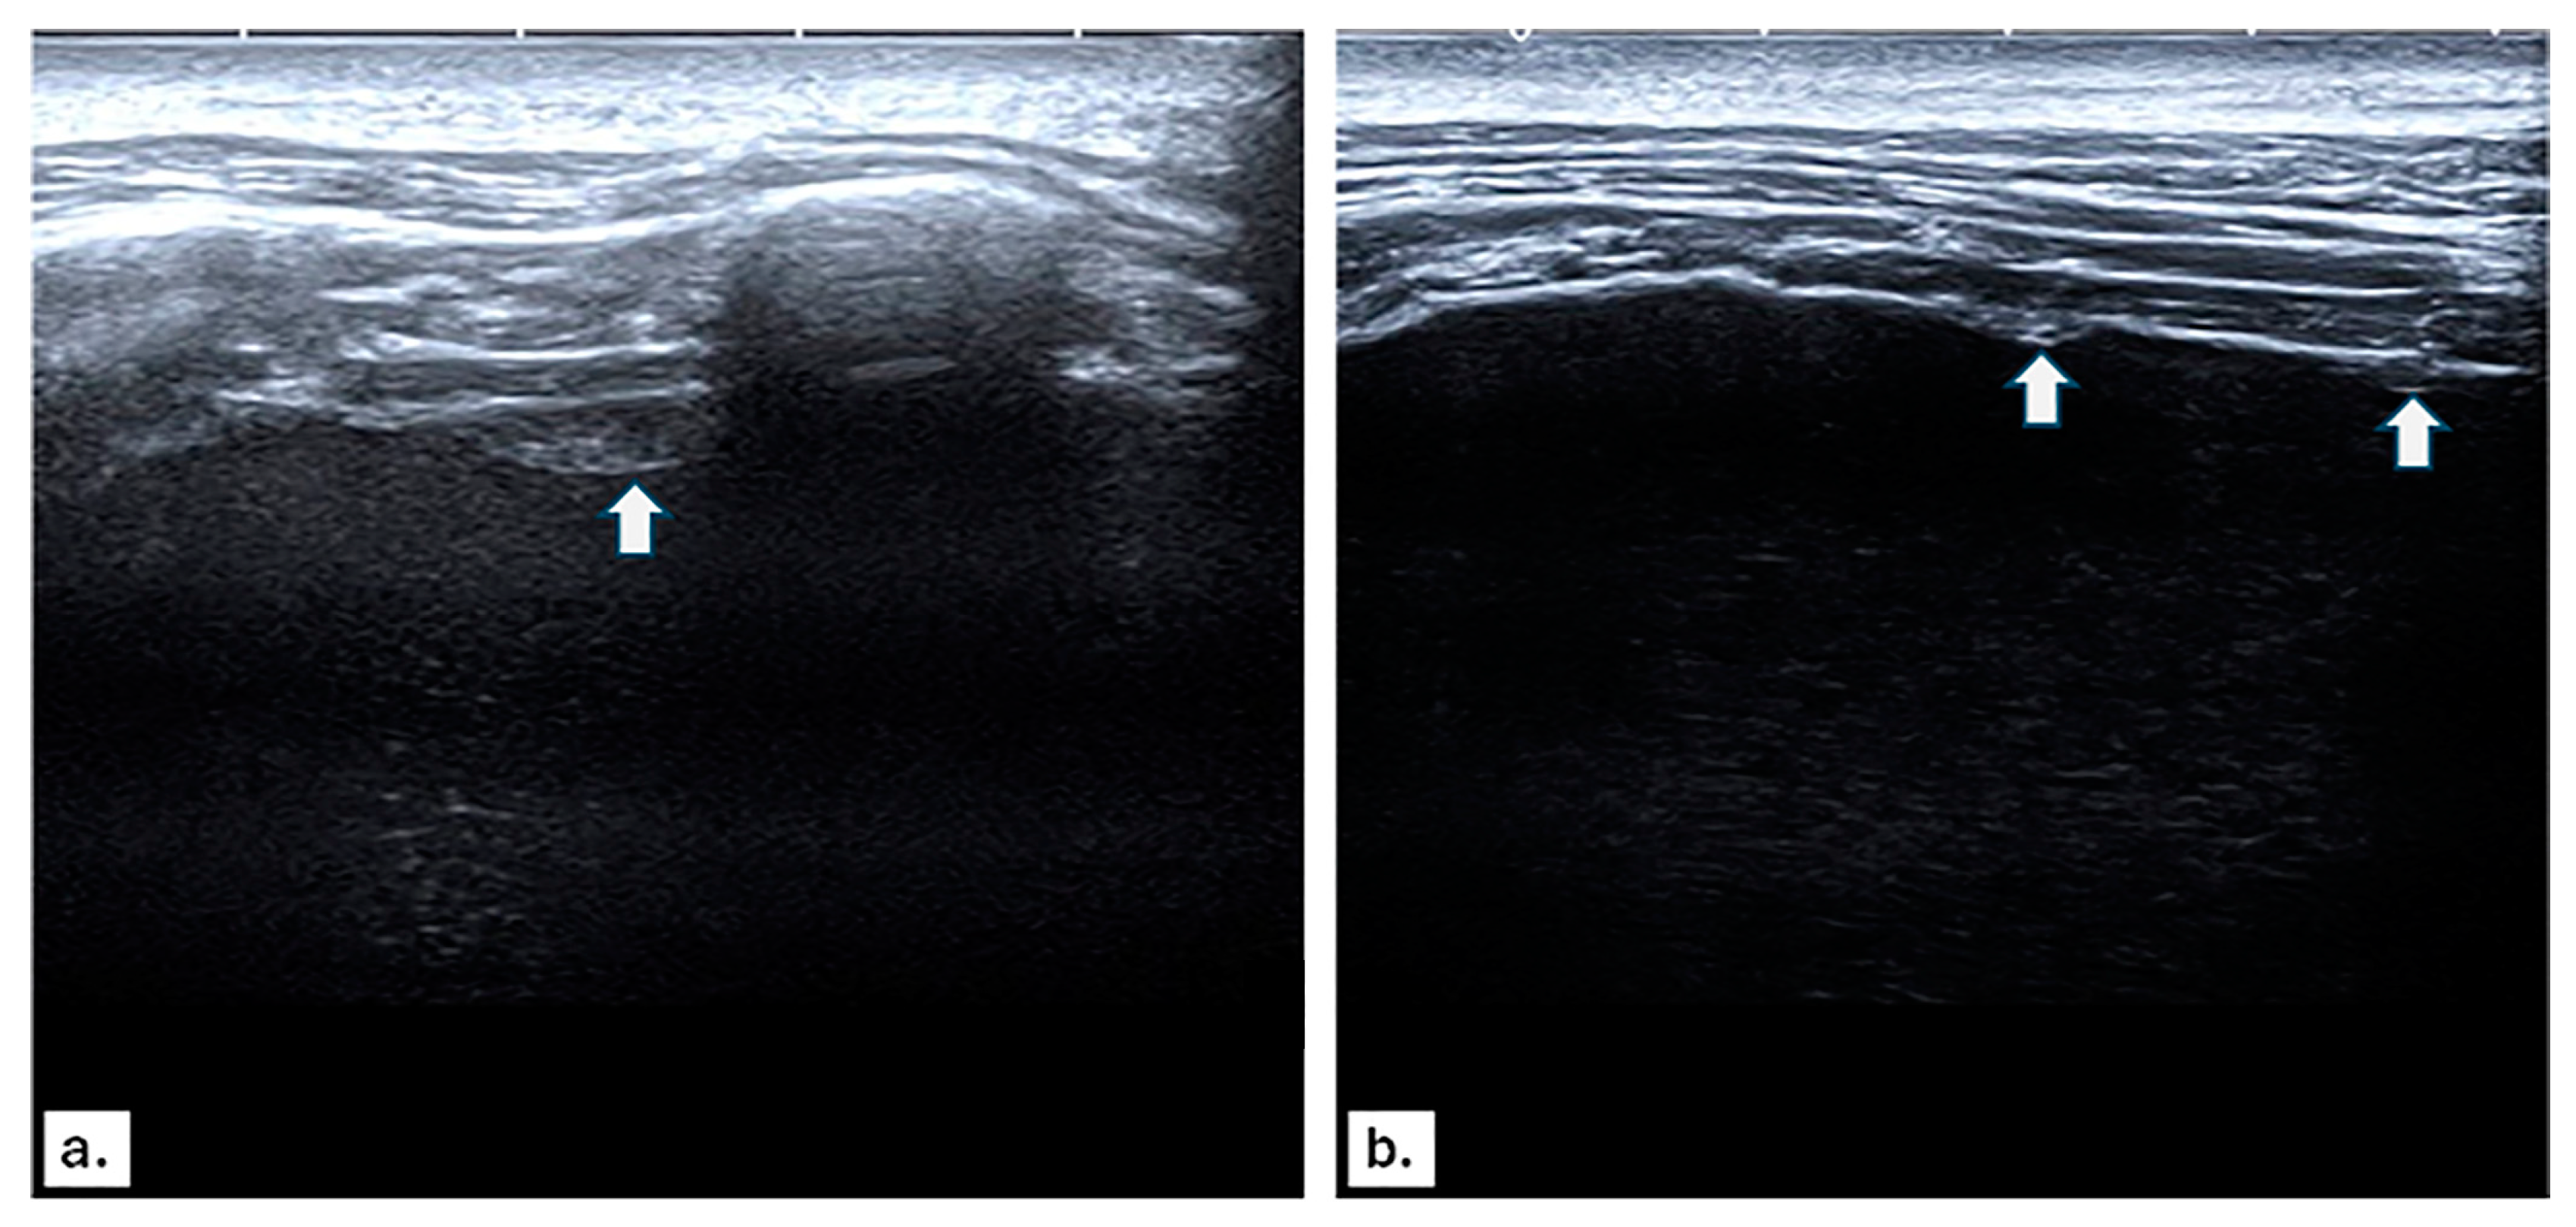

2.3. Chest US Protocol

3.2. US and CT Findings in MPE

3.3. Imaging Findings in Benign Pleural Effusion